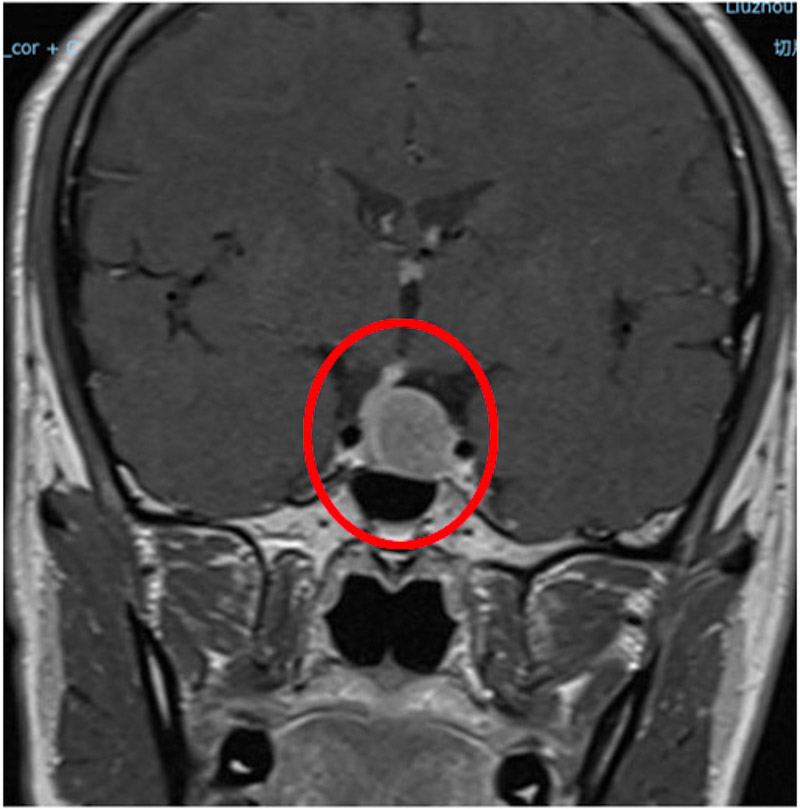

患者病灶大小約為13mm×23mm×20mm,考慮垂體大腺瘤。為徹底解決韋先生面臨的難題,垂體腫瘤MDT團隊開展了多次討論,認為患者病變累鞍內(nèi)及鞍上,侵襲視交叉及兩側(cè)海綿竇受壓,建議手術(shù)治療。